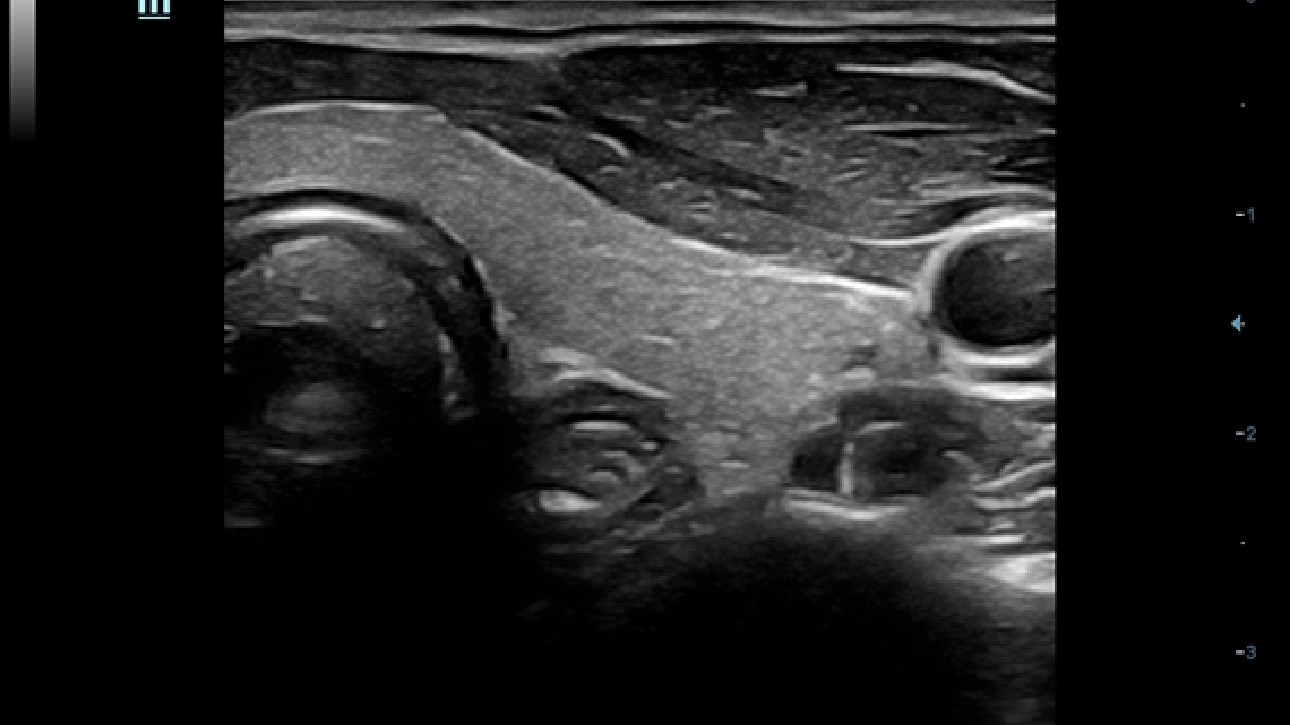

?????? ??? ???? ?? ???? ??? ??? ??? ???? ??? ??? ??? ?? ??? ???? ?????. ??? ?? ????? ???? ???? ??? ?? ??? ???? ?? ???? ??? ???? ???? ????.

???? ?? ??? ?????, X-Insight???? ??? DC-60 Exp ?? ??? ???? ???? ?? ??? ?? ??? ?? ???? ?????.